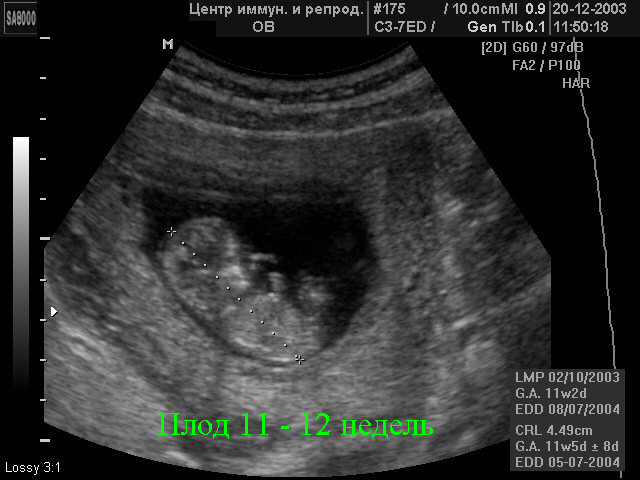

В общем вымахали. Показали мне картинку. Аж дыхание захватывает, еще на полный монитор изображение. Вот типа такой картинки я увидела: